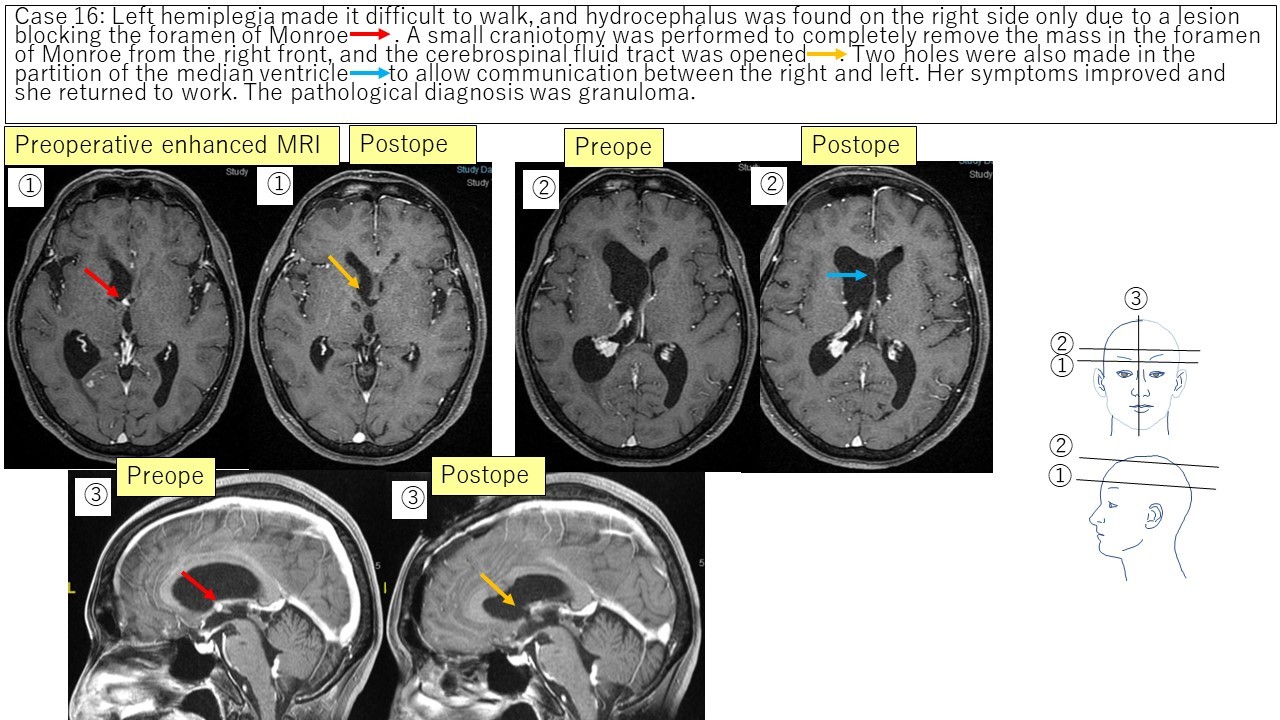

③ Intraventricular tumor (Monroe granuloma) Case 16